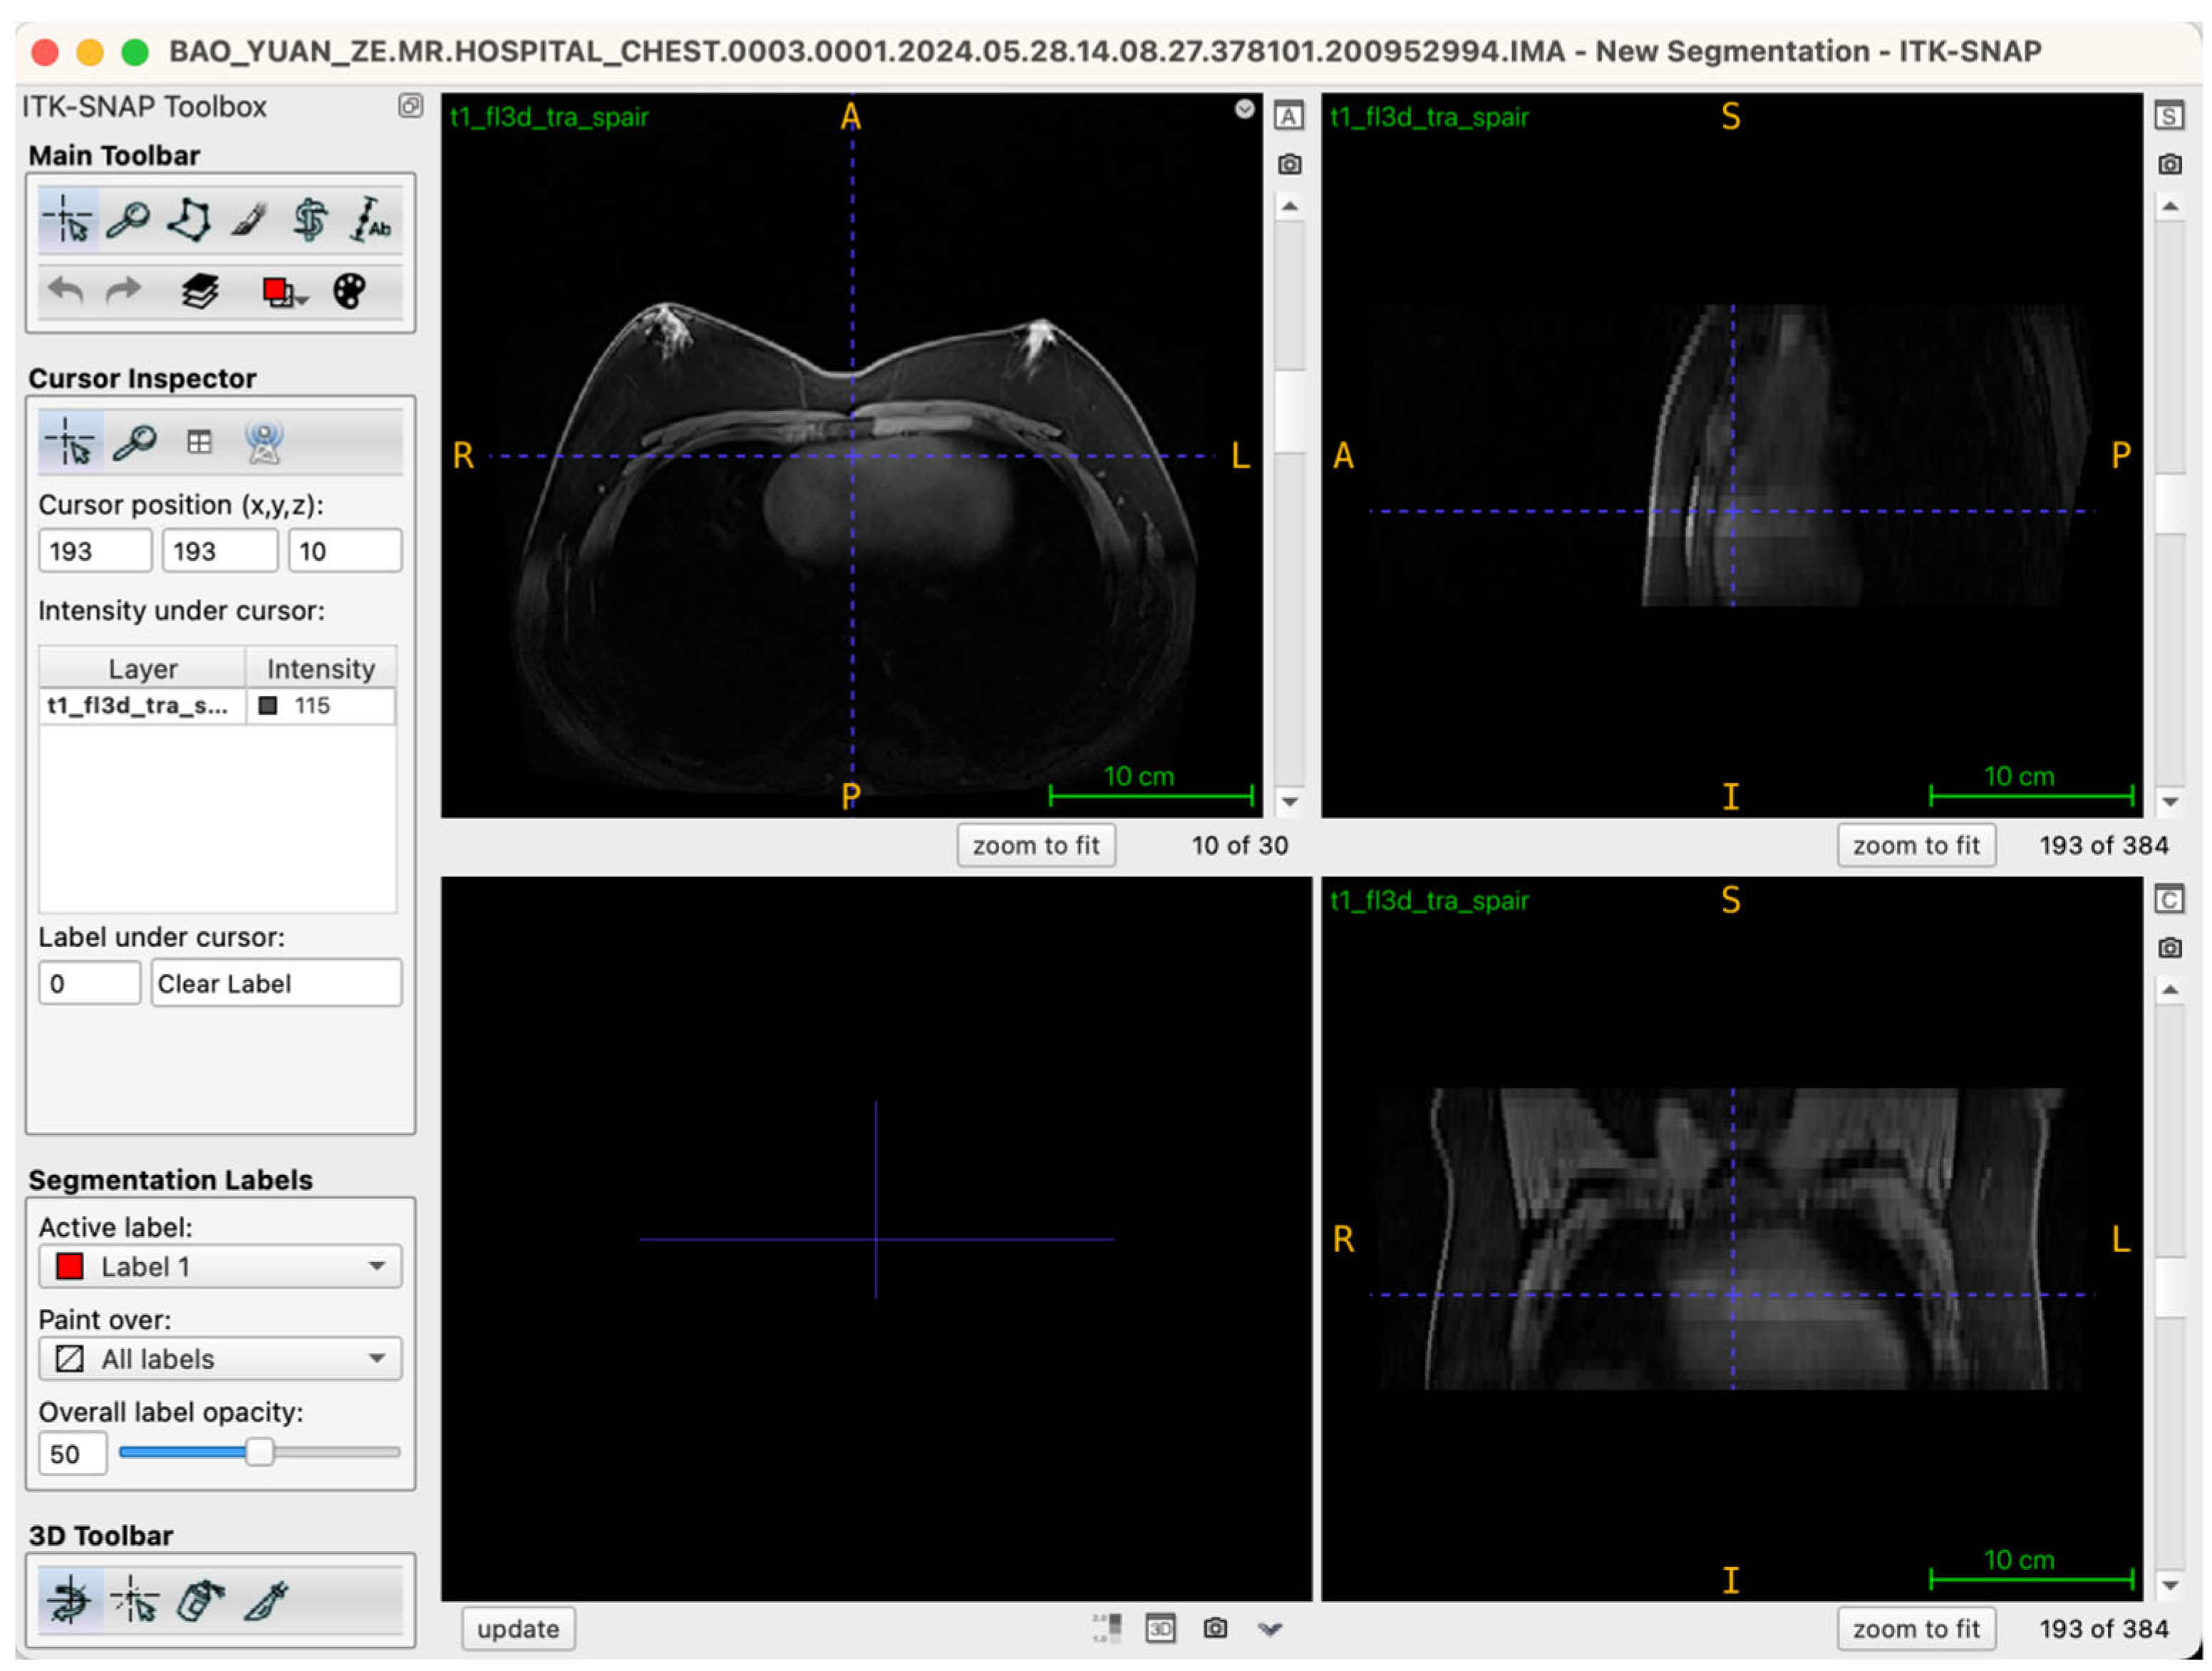

Selecting an appropriate viewing strategy and incorporating cross-plane validation within ITK-SNAP 4.0 software are crucial for achieving accurate structural identification in three-dimensional breast tissue segmentation. The MRI data employed in this study comprised a T1-weighted three-dimensional fat-suppressed sequence (t1_fl3d_tra_spair) with complete spatial information. Images were originally acquired in the axial (transverse) plane, consisting of 30 continuous slices without gaps, ensuring anatomical continuity and spatial coherence.

During segmentation, the axial view served as the primary reference plane by default for structural identification and segmentation operations. This choice was based on the clear visualization of breast glandular tissues—which typically present as medium-to-high signal intensity areas—providing clearly discernible boundaries in axial slices. Thus, most seed-point placements, region-growing steps, active contour (Snake) model iterations, and manual corrections were conducted in this plane. To further ensure spatial consistency and anatomical precision of the segmentation boundaries, the Multi-Planar Reformatting (MPR) mode was simultaneously activated throughout the segmentation process, synchronously displaying coronal, sagittal, and axial views (Figure 2). The interactive linkage among these three planes allowed operators to monitor tissue morphology and spatial extension in real-time across different orientations. Particularly in transitional anatomical regions—such as breast margins, pectoral muscle interfaces, and subcutaneous adipose tissue edges—this approach significantly enhanced boundary delineation accuracy. By cross-validating seed-point positions and the progression of segmented boundaries across different views, potential misclassifications, artifacts, or structural discontinuities were promptly identified and rectified during segmentation, thus markedly improving the anatomical fidelity of the final three-dimensional reconstruction. Additionally, this multi-planar visualization approach laid an essential foundation for subsequent reverse rendering-based quality control, allowing operators to verify structural coherence across all imaging planes comprehensively.

Figure 2.

Illustration of the workstation interface utilizing multi-planar reformatting views.